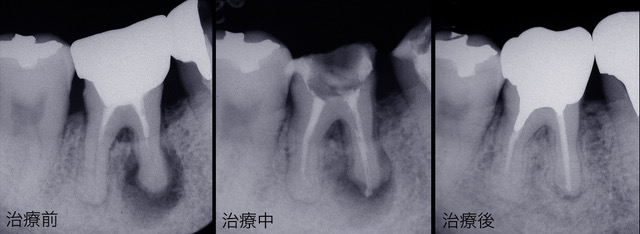

上のレントゲンでは根の先端に大きな病巣があるのがわかります。右側が治療後ですが病巣が消えています。歯を入れるだけでなくレントゲンで骨の状態の改善が確認できなければ本当に治ったとは言えません。

神経を取ったはずの歯がまた痛みだすことがあります。これは神経の入っていた根の中にある細い管に残ったばい菌が根の先にある噛み心地を感じる神経や骨を刺激しておこる痛みです。この根の治療には細い針を何種類も使って手作業で行う細かい作業で根気のいる治療です。根の先にピッタリと薬を過不足なく入れることが治療の目標ですが、根の形は曲がったり先で分岐してたりで100%上手くいくとは限らず痛みが出てしまうことがあるのです。根の治療が上手くいかなければその上にどんな高価な歯を入れても無駄になってしまいます。須貝歯科医院では出来るかぎり根の先までしっかり薬で埋められるように電気的測定メーターやレントゲンで確認しながら治療を進めています。それでも100%上手くいくわけではないので再治療することも考慮に入れて上に入れる土台や被せ物も選択しています。